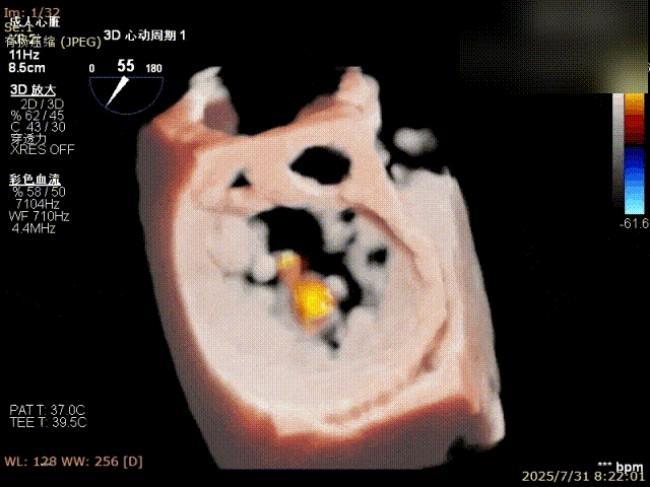

三维评估

二尖瓣P1脱垂偏心性返流术前影像